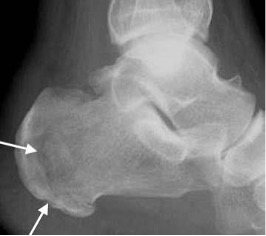

Progressive calcaneal osteomyelitis with ill-defined radiolucency progressing to bone destruction (arrows). Skin ulcers are apparent (arrowheads)